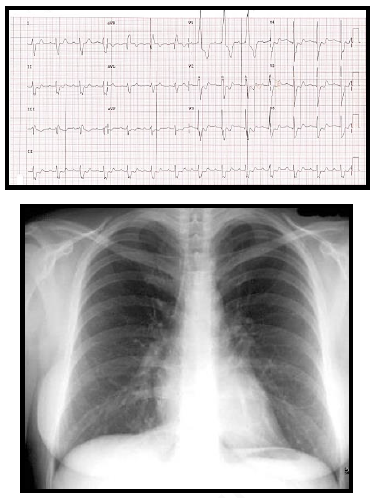

Paciente de 34 anos, G3P1A2, no décimo dia de

puerpério, deu entrada no pronto socorro com

queixa de dor torácica associada a dispneia

importante. Ao exame físico apresenta regular

estado geral, corada, hidratada, afebril,

ausculta pulmonar sem alterações, taquipneia

(frequência respiratória de 30 ipm) com

saturação de oxigênio de 84% em ar ambiente,

ausculta cardíaca sem alterações, frequência

cardíaca de 108 bpm e pressão arterial de 86 x

54 mmHg. O eletrocardiograma e o RX de tórax

estão demonstrados nas figuras abaixo. Os

exames laboratoriais demonstram Troponina =

0,9 mcg/dl (Valor normal < 0,01 mcg/dl) e

Peptídeo Natriurético Cerebral (NT pró-BNP) =

1314 pg/dl (Valor normal < 200 pg/dl).

Sobre o diagnóstico mais provável, assinale a alternativa correta.